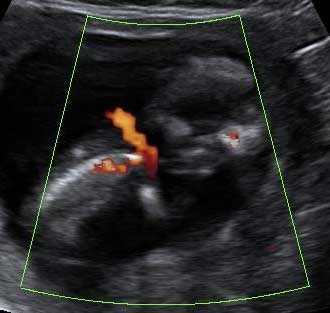

Ecografía 2D de la semana 12: Feto con el cordón umbilical alrededor del cuello

En las ecografías se pueden ver las vueltas de cordón umbilical alrededor del feto. Son muy frecuentes, y no suelen suponer riesgo para el bebé dado que el cordón es muy gelatinoso.

Feto de 12 semanas con cordón al cuello

Circular de cordón umbilical (en color sepia) alrededor del cuello de un feto con una edad gestacional de 12 semanas.